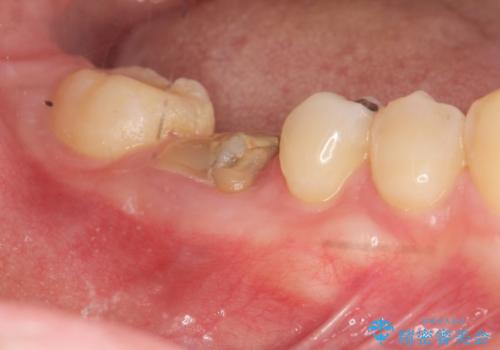

[ インプラントによる機能回復 ] 強い咬合力 放置した虫歯の治療

![[ インプラントによる機能回復 ] 強い咬合力 放置した虫歯の治療の症例 治療前](https://seimitsushinbi.jp/wp/wp-content/uploads/2022/07/dbc5e5b52dd96aeab54aa69e57a96bd1-500x350.jpg?v=1658988380)